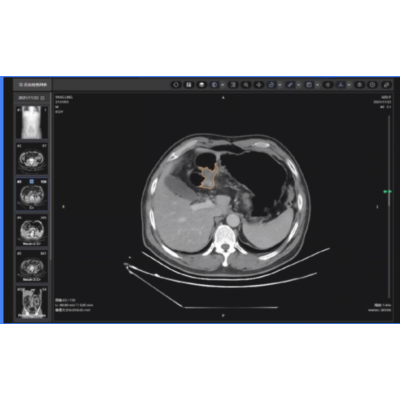

胃癌 GastroSense Al 知未分度

新辅助治疗疗效评价;

临床分期诊断;

生存预测。